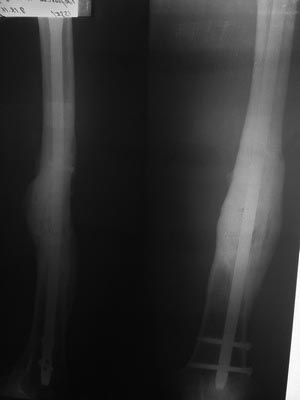

Итоги лечения многооскольчатого перелома бедра

Делюсь отдаленным результатом лечения многооскольчатого перелома бедра (случай публиковался на форуме в феврале 2016

В феврале сделана костная аутопластика (расщеп малоберцевой кости + крыло подвздошной кости) + аллопластика + PRF. От динамизации убежал.

На сейчас: жалоб нет, полная нагрузка, спорт. Травма 26.09.2015, закрытая репозиция, БИОС PFNA Long 28.09.2015, февраль 2016 - костная пластика. Ссылка на медиаресурс http://dropmefiles.com/vTXbx